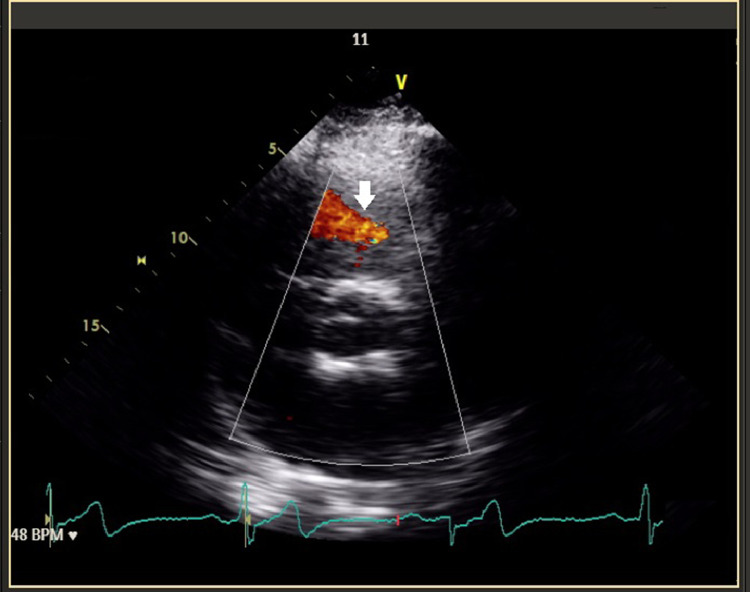

Fig. 2.

Pulmonary regurgitation on echocardiography: pulmonary artery aneurysm can result in pulmonary regurgitation which can be observed as blood flow in the echocardiogram above (white arrow).